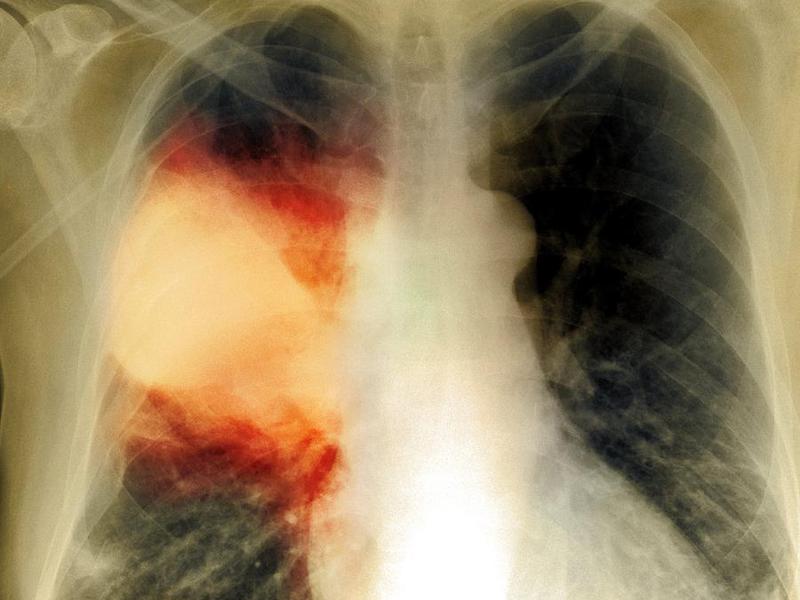

- Крупозная пневмония. Наблюдаются изменения нормального легочного рисунка, жидкость в полости плевры, признаки инфильтрации одной из долей легкого, расширение корней. По мере развития воспалительного процесса выраженность изменений и интенсивность окраски затемнений усиливается.

- Абсцедирующая пневмония. Проявляется обширным затемнением пораженной области, признаками утолщения плевры и наличием полостей разного размера, наполненных жидкостью.

- Стадия опеченения. Ткани легких уплотняются, и становится похожей на ткани печени. Рисунок легких на данной стадии выражен не так интенсивно, на нем формируются темные пятна со светлыми полосами, корни органа расширены, причем особенно это заметно на пораженной стороне. По мере развития патологического процесса очаги воспаления затемняются, а наличие жидкости хорошо заметно на снимках.

Как правило, при крупозной форме воспаления легких поражается одна или несколько долей легких сразу. Это создает серьезную угрозу жизни пациента.

На рентгене крупозная форма болезни проявляется следующими признаками:

- Ярко выраженные крупные тени, затрагивающие доли легкого целиком. Могут быть поражены оба легкого.

- Средостение смещается в сторону наиболее воспаленного легкого.

- На куполах диафрагмы отчетливо видны признаки деформации.

- Рисунок легочной ткани может не просматриваться.

Крупозная пневмония легче всего выявляется при рентгенологическом исследовании. Тем не менее для постановки точного диагноза врачи предпочитают делать рентгеновские снимки в двух проекциях. Это дает им возможность определить число пораженных воспалением сегментов органа и определить состояние средостения.